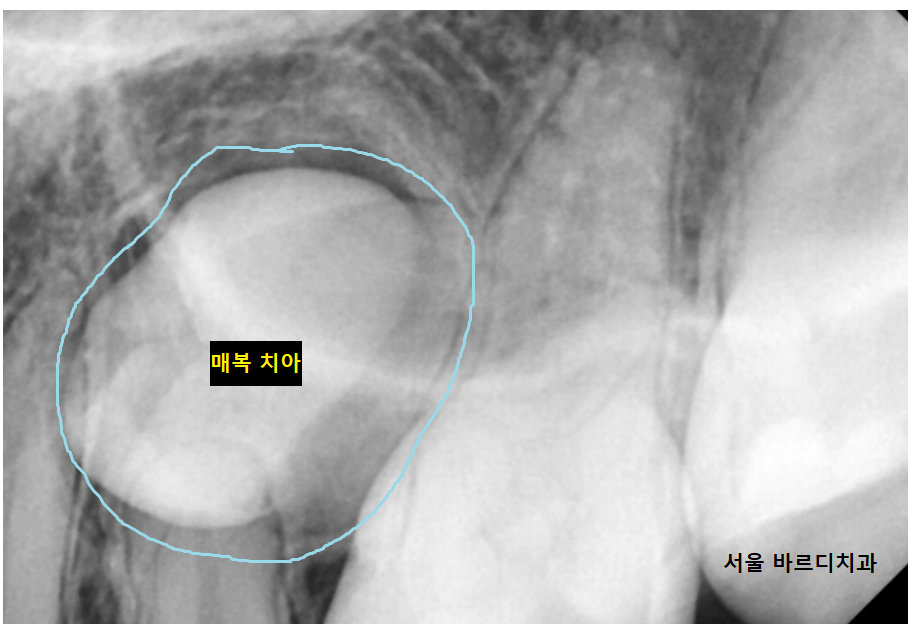

23.07.31

주변 치아에는 문제가 없나

x-ray를 통해 최최종 확인을 하고

덕풍동 치과에서

숨어있는 매복치 수술 진행했습니다.

주변 치아에 손상이 가지 않게

조각 조각 나누어 뽑아 주었습니다.

깔끔하게 잘린 단면 보이시죠?

이게 기술입니다!

잘 안뽑히게되면 조각 조각 부수어가면서 뽑아야하는데

교정 발치 시간도 오래 걸리고

주변 뼈도 많이 갈아내야해서

환자분이 뽑고 나서 힘들어하실 수 있습니다.